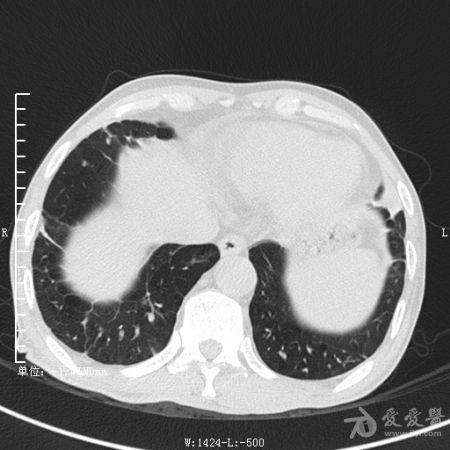

典型支气管扩张及肺水肿CT片

典型支气管扩张肺水肿